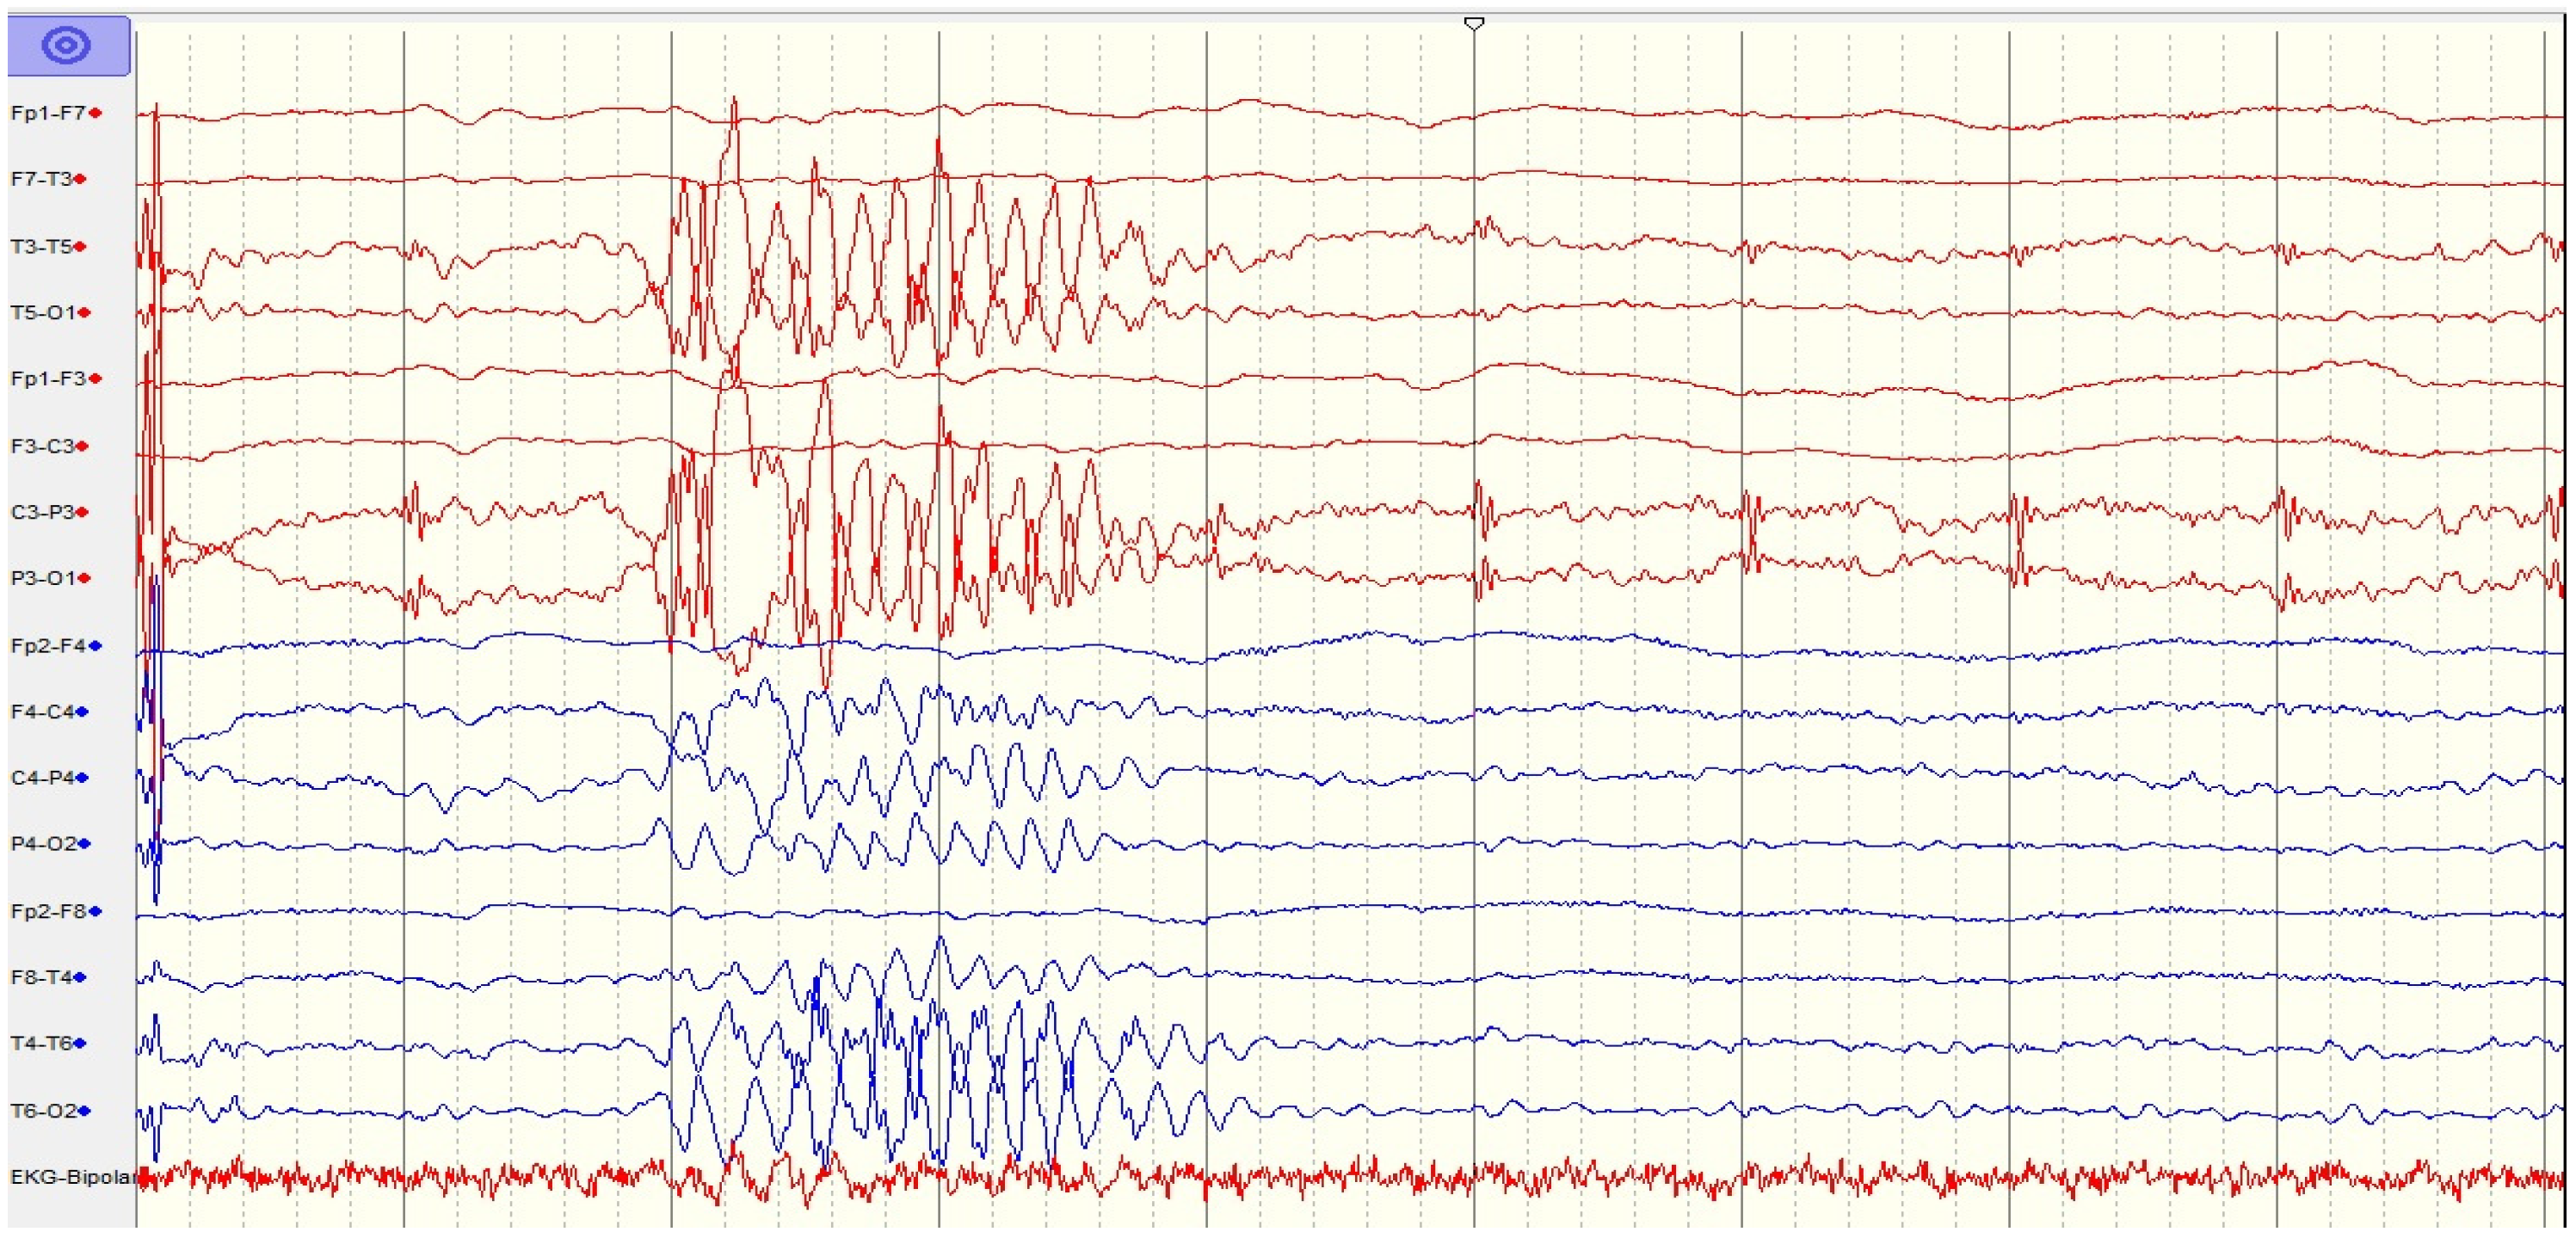

Longer-range EEG monitoring (Figure 2) showed an epileptogenic pattern with generalized positive sharp waves (PSWs). However, after parenteral antiepileptic drugs (AEDs) were administered (levetiracetam, sodium valproate, and clobazam), the EEG results became worse, and supportive EEG findings confirmed convulsive status epilepticus. A semi-quantitative method was applied to detect the presence of anti-NMDAR antibodies in the serum and CSF, with a positive result (Table 4). After the diagnosis of anti-NMDAR encephalitis was confirmed, first-line immunotherapy including intravenous methylprednisolone (1 g daily for 5 days), two cycles of intravenous immunoglobulin (0.4 g/kg/day for 5 days during the first cycle and 2 g/kg/day for 3 days during the second cycle, with a distance of 6 weeks), and plasma exchange (one session every other day for two cycles) was administered, though this did not yield an adequate response. Using the Glasgow coma scale (GCS) to evaluate loss of consciousness, we found that she had a score of 4–5 with autonomic dysfunction (hypotension + tachycardia) and central hypoventilation. She was also noted to have brief episodes of tonic–clonic seizure activity necessitating critical anesthesiologist care. Acute respiratory failure led to emergent endotracheal intubation, including mechanical ventilation. Intravenous continuous anesthetic therapy with thiopental was administered for sedation, as well as for the treatment of refractory status epilepticus.

Figure 2. EEG findings of generalized PSW complexes.